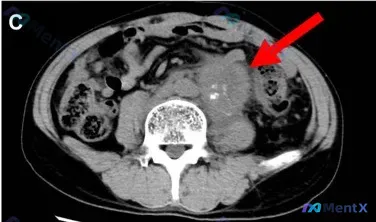

这是一份腹部CT横断面影像:

- 定位:腹膜后脊柱前方,腹主动脉旁及左侧

- 形态:边界相对清晰的类圆形/分叶状软组织肿块

- 关键征象:

- 肿块内部可见多发点状、团块状高密度钙化灶(极亮白区域)

- 肿块对周围腹主动脉及分支有包裹/推挤效应

- 其他:未见明显腹腔游离气体或大量积液